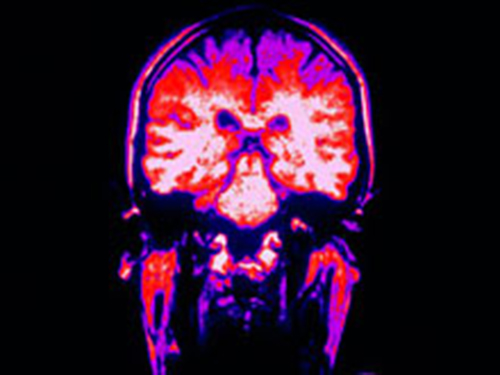

Новый метод позволит«сфотографировать» активность всего мозга

Его разработали ученые из Рокфеллеровского университета. Специалисты говорят: используя новую технику, можно запечатлеть все активные нейроны в головном мозге в определенный момент времени. Метод уже протестировали на мышах, сообщает The Times of India.

По словам исследователей, в мозге мышей десятки миллионов нервных клеток. На одном снимке видна активность примерно одного миллиона нейронов. Новый метод не дает возможности наблюдать за активностью мозга в режиме реального времени. Однако несколько снимков при необходимости можно сравнить.

Специалисты предлагают использовать данный метод для оценки изменений в мозговой активности, например, в случае болезни или при приеме лекарств. Ученые надеются, что новая техника поможет узнать больше о работе мозга.